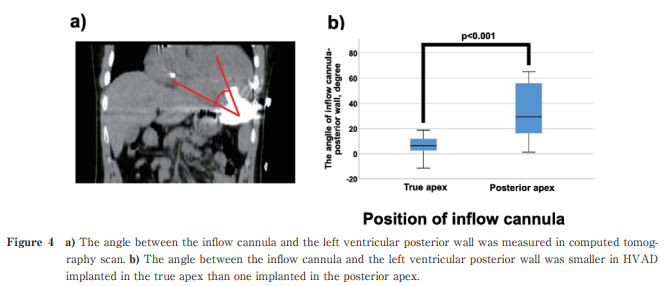

Mid-term Outcome of HeartWare HVAD in Small Patients in Japan

https://doi.org/10.51040/dkmj.2024-019

Yuji Sakashita et al.

Published online : December 26 , 2024